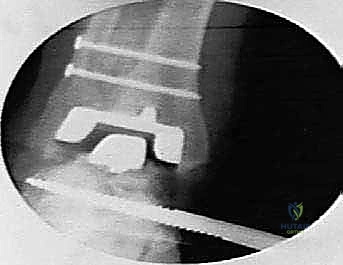

1. مكون ظنبوبي (Tibial Component): قطعة معدنية تُثبت في عظمة الساق (القصبة). الميزة العبقرية لنظام Agility هي أنه يتطلب دمج المفصل الظنبوبي الشظوي السفلي (Tibiofibular syndesmosis). هذا يعني أن الجراح يقوم بدمج عظمة القصبة مع عظمة الشظية لإنشاء قاعدة عريضة وقوية جداً تدعم المفصل الصناعي وتمنع ارتخاءه بمرور الوقت.

2. مكون كاحلي (Talar Component): قطعة معدنية تُثبت في عظمة الكاحل، مع وجود سطح بلاستيكي عالي الكثافة (البولي إيثيلين) بين المكونين لضمان انزلاق سلس وحركة طبيعية.

هذا التصميم الواسع يوفر استقراراً دورانياً فائقاً، ويقلل من الضغط المتركز على نقطة واحدة، مما يزيد من العمر الافتراضي للمفصل الصناعي.

4. تحضير العظام ودمج القصبة والشظية

هذه هي الخطوة الأكثر حيوية في نظام Agility. يتم إزالة الغضروف التالف والزوائد العظمية. ثم يتم تحضير السطح السفلي لعظمة القصبة (Tibia) والسطح العلوي لعظمة الكاحل (Talus) باستخدام أدوات قطع دقيقة لضمان ملاءمة مثالية للمفصل الصناعي. بالتوازي، يتم تجهيز المسافة بين القصبة والشظية ووضع طعوم عظمية (Bone Grafts) لضمان التحام العظمتين معاً، مما يشكل قاعدة صلبة للمكون العلوي.

5. زراعة المفصل الصناعي (Implantation)

يتم إدخال المكون الظنبوبي (العلوي) والمكون الكاحلي (السفلي) وتثبيتهما بإحكام. يتم إدخال القطعة البلاستيكية (البولي إيثيلين) بينهما. يقوم الدكتور هطيف باختبار حركة المفصل وتوازنه وشد الأربطة لضمان استقرار المفصل في جميع الاتجاهات.